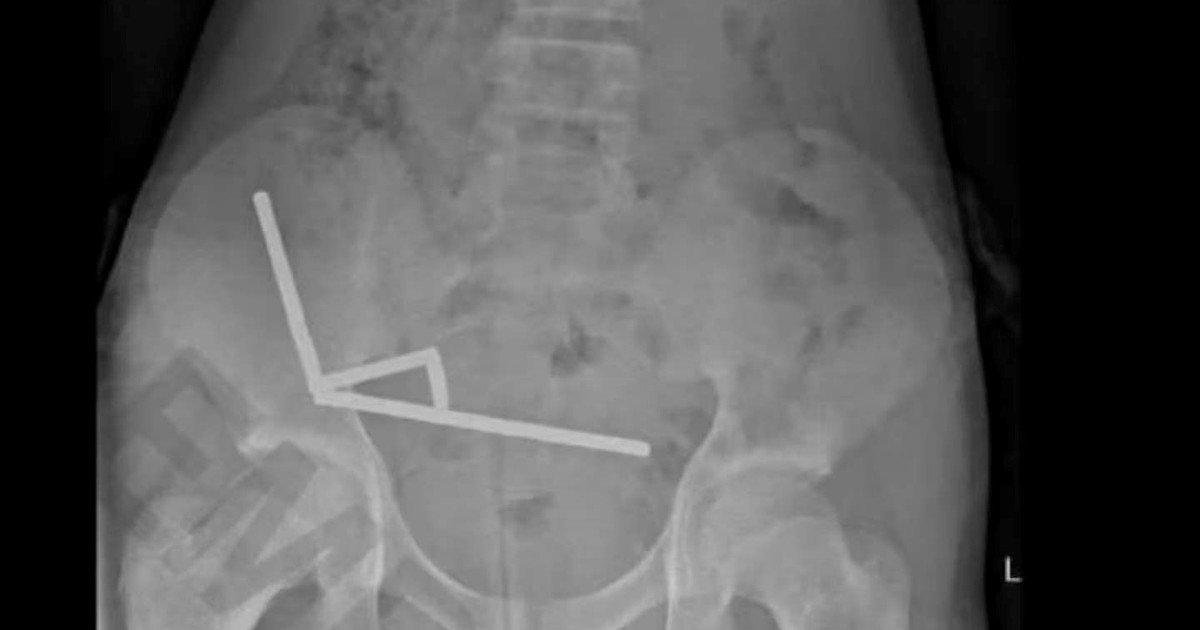

• Los imanes más peligrosos del mercado se le unieron dentro del cuerpo.

• ¿Qué son los imanes de neodimio y qué tan grave es su ingesta?